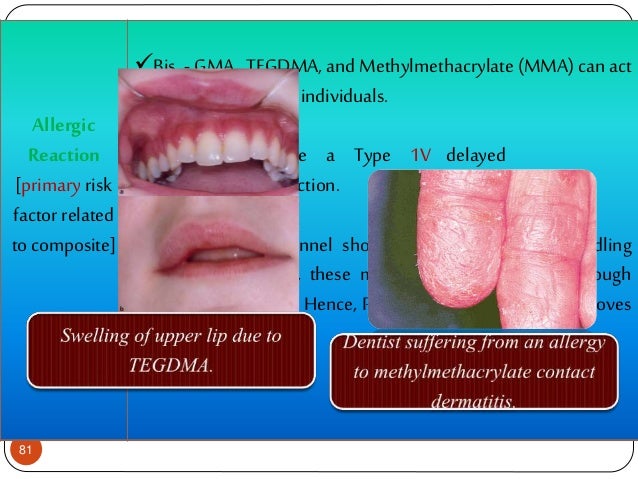

biocompatibility composite reaction allergic

Allergy And Autoimmune Diseases In Dentistry

www.slideshare.net

www.slideshare.net

allergy dentistry autoimmune diseases dermatitis